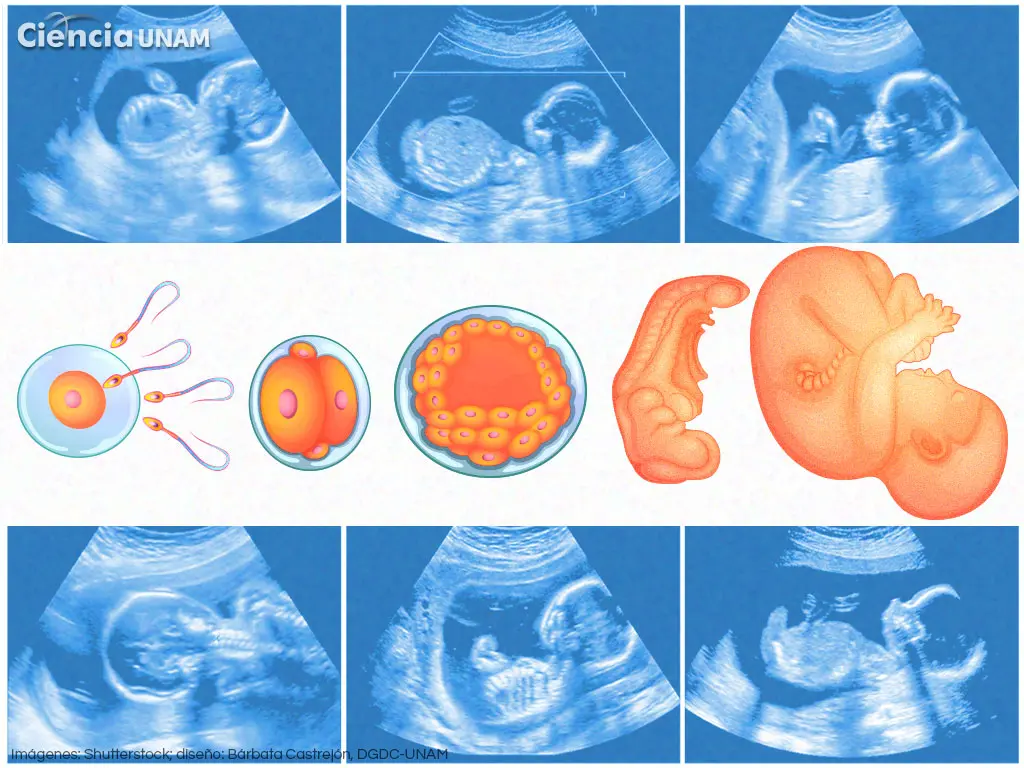

La embriología es el estudio del desarrollo del embrión desde la fecundación hasta la formación de los principales órganos. Este proceso, que empieza con la unión del espermatozoide y el óvulo (fecundación), da origen al cigoto, una célula única que contiene toda la información genética necesaria para el desarrollo de un nuevo ser humano. El desarrollo embrionario se divide en diferentes etapas: la fecundación, la etapa embrionaria (de la tercera a la octava semana) y la etapa fetal (desde la octava semana hasta el nacimiento). Cada una de estas etapas se caracteriza por eventos específicos y cruciales para el desarrollo normal del feto.

Etapas del Desarrollo Embrionario:

- Fecundación: Unión del espermatozoide y el óvulo.

- Etapa Embrionaria: Desarrollo de los principales sistemas de órganos (de la tercera a la octava semana).

- Etapa Fetal: Maduración y crecimiento de los órganos y sistemas (desde la octava semana hasta el nacimiento).

El libro Moore Embriología detalla cada una de estas etapas con precisión, proporcionando al lector una comprensión profunda de los procesos involucrados en la formación de un ser humano. A lo largo de su desarrollo, el embrión es vulnerable a diversos factores, incluidos los teratógenos (agentes externos que pueden causar malformaciones congénitas), lo que enfatiza la importancia de la salud materna durante el embarazo.